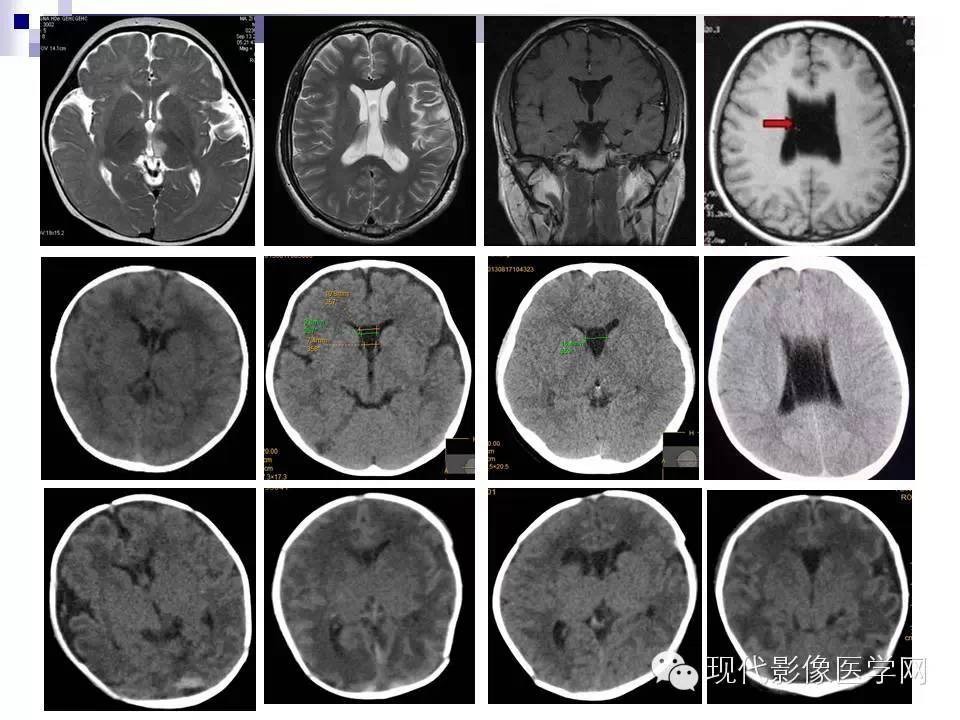

透明隔缺失影像学表现,透明隔腔影像